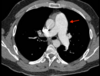

• Enfisema

• Neumotorax

How well did you know this?

1